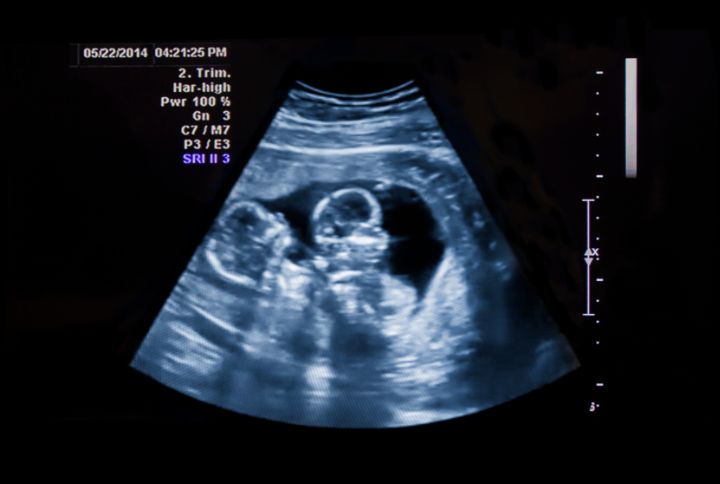

La future maman découvre généralement qu'elle est enceinte de plusieurs fœtus lors de l'échographie du 1er trimestre. Parfois, certains signes peuvent la mettre sur la voie (fatigue, intensité des symptômes, taille du ventre), mais il est important, si elle le souhaite, de le vérifier. Les grossesses multiples sont des grossesses rares et considérées comme plus à risque.

Les grossesses gémellaires bénéficient d’un suivi échographique plus poussé, avec des échographies régulières (en général, une par mois). Dès les premières échographies, le médecin peut déceler si la grossesse gémellaire est une grossesse monochoriale ou bichoriale (un seul ou deux placentas). Il est important de préciser que les premières échographies sont très importantes en cas de grossesse gémellaire, car certaines structures permettant de définir le type de grossesse gémellaire ne sont visibles qu’au premier trimestre (recherche du signe lambda par exemple relatif à la présence de la membrane interamniotique).